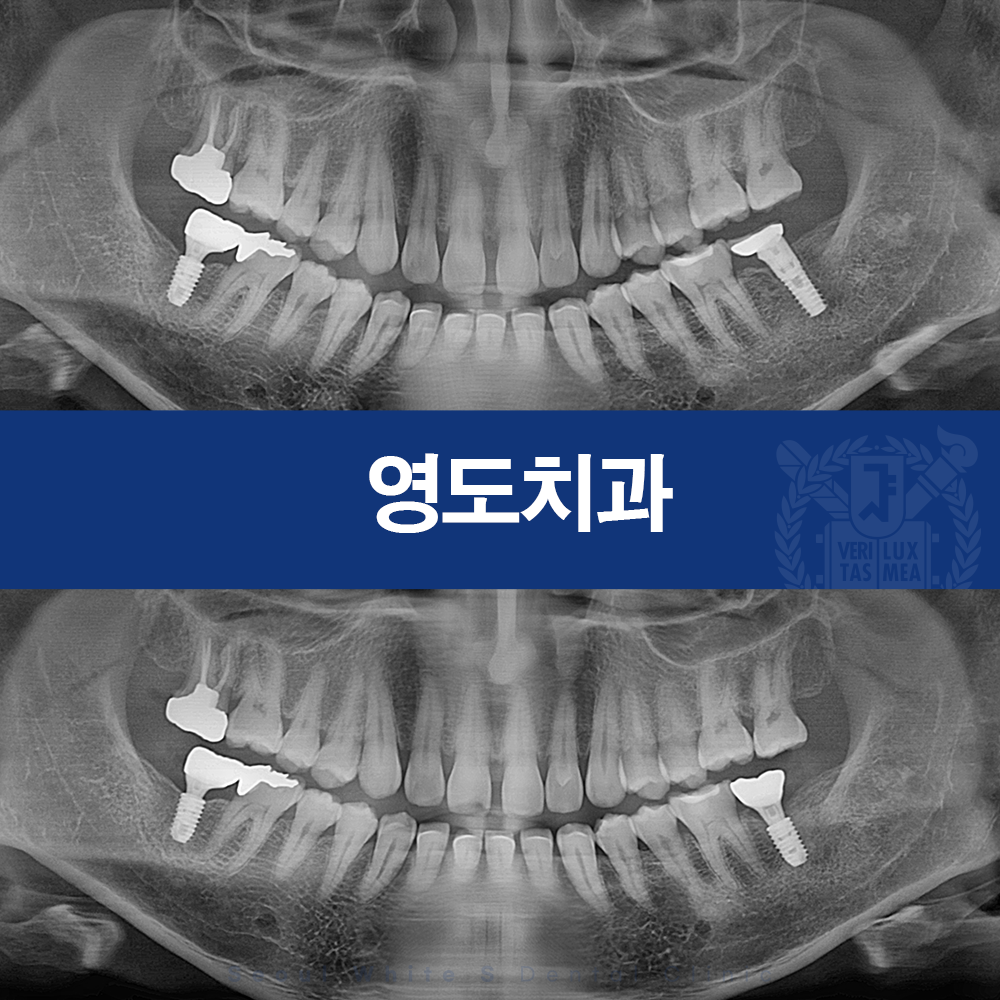

술전 사진

(24.11.18)

내원 당시 촬영한 사진을 보면 오른쪽 아래, 즉 #37 부위에 식립된 임플란트에 문제가 발생한 상태임을 확인할 수 있었습니다.

사진상 왼쪽 아래 임플란트 역시 이상적인 상태라고 보기는 어렵지만, 특히 오른쪽 하악 부위 임플란트는 뿌리 주변으로 염증이 상당히 진행된 모습이 뚜렷하게 관찰되었습니다.

방사선 사진을 살펴보면 임플란트 주위가 음영으로 보이며, 지지해야 할 뼈가 소실되면서 임플란트 상단이 이미 골 상방으로 많이 노출된 상태임을 알 수 있습니다. 게다가 환자분께서 저작 시 불편감까지 호소하고 계셨기 때문에, 기존 보철물의 형태 역시 함께 점검하고 조정할 필요가 있는 상황이었습니다.

술후 사진

(25.07.30)

재식립 후 확인해 보니 기존에 사용하시던 보철물에 비해 형태와 균형이 훨씬 개선된 모습을 보였고, 환자분께서 호소하시던 편감도 함께 해소되어 현재는 매우 만족해하시며 정기적인 내원 관리를 이어가고 계십니다.

- 임플란트 주변에 남아 있던 염증을 충분히 제거한 뒤 보다 안정적인 위치로 골 하방에 재식립한 점

또한 최근 임상 흐름에 맞춰 과도하지 않은 적절한 길이의 임플란트를 선택함으로써 불필요한 뼈 손실을 최소화하며 보다 안정적인 치료가 가능했습니다.